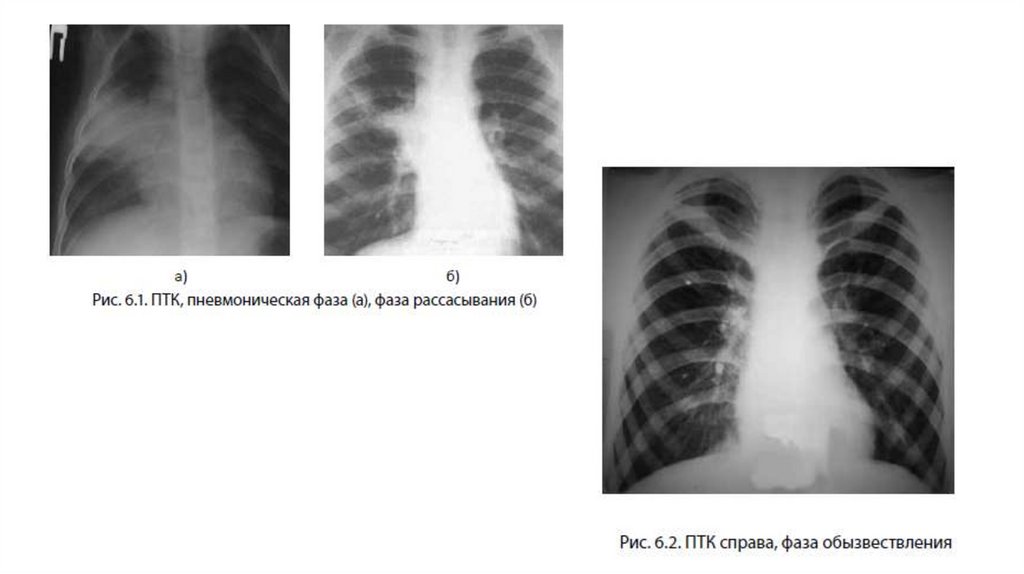

5. На рентгенограмме:

в начале болезни выявляется участок затенения

легочной ткани, связанный воспалительной дорожкой с

расширенным корнем легкого, напоминающий

пневмонию (пневмоническая фаза).

Через 1–2 месяца отмечается частичное рассасывание

воспаления, при этом четко выявляется легочный

компонент и увеличенные регионарные лимфатические

узлы в средостении (фаза рассасывания)

Через 12 месяцев лечения и наблюдения участок

воспаления в легких частично рассасывается, окружается

плотной фиброзной капсулой и обызвествляется (фазы

уплотнения и обызвествления с формированием

кальцинатов). Похожие изменения происходят и в

регионарных лимфатических узлах.